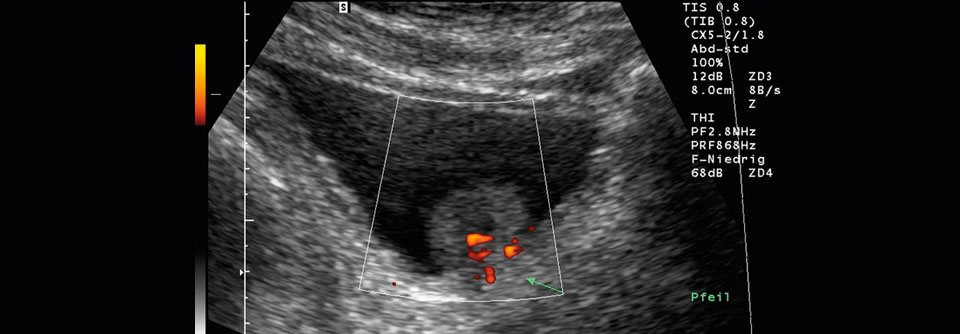

Wie hoch ist der klinisch relevante Überlebensvorteil der PSA-Bestimmung? Wie hoch ist der klinisch relevante Überlebensvorteil der PSA-Bestimmung? © iStock/Shidlovski, MicroStockHub